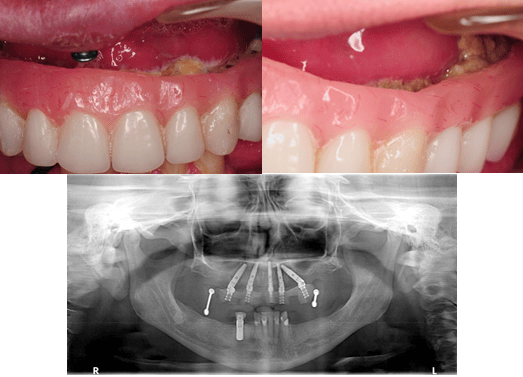

Case Example 3

Full-arch implant therapy in a transitional denture supported by five implants

Implant dentistry is especially sought after by the edentulous population or patients with a terminally ill dentition. The transitional phase of implant therapy (where a patient is in a provisional or temporary restoration during osteointegration) is a crucial time for the patient to be seen by a dental hygienist. This will help uncover any inadequacies in restorative design that may complicate home care before the final restoration is delivered.

This case is an example of a poor transitional design that made at-home maintenance impossible for the patient. All five implants developed peri-implantitis and were removed only four months after placement.